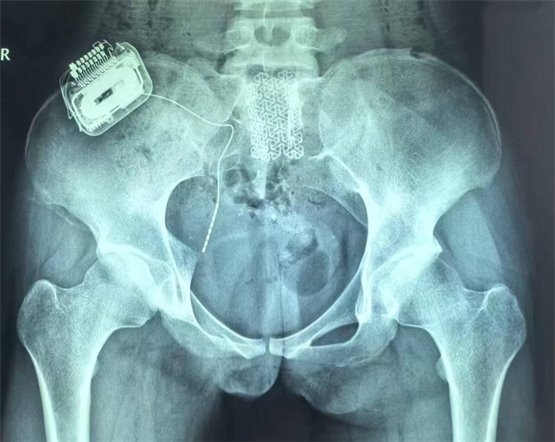

鑒于一期手術(shù)的良好療效,患者家屬?zèng)Q定進(jìn)行二期永久植入,將骶神經(jīng)電極及脈沖發(fā)生器永久性植入患者體內(nèi)。二期手術(shù)后,患者白天已經(jīng)無(wú)漏尿,夜間偶有遺尿(目前仍在調(diào)整過程中,希望通過調(diào)整合適的刺激參數(shù),后續(xù)能夠得到更好的改善);排尿費(fèi)力感減輕(術(shù)前為點(diǎn)滴狀,現(xiàn)尿線變粗,最大排尿量達(dá)220ml);肛門周圍已恢復(fù)部分感覺,整體改善非常顯著。

圖4為骶神經(jīng)調(diào)控術(shù)后骨盆正位片